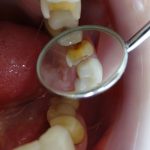

銀歯の横から虫歯に

• 2025年04月23日

• プレミアムセラミック CERECオムニカム

術前   銀歯の詰め物の横から虫歯になり黒くなっています。 銀歯の横の歯が虫...